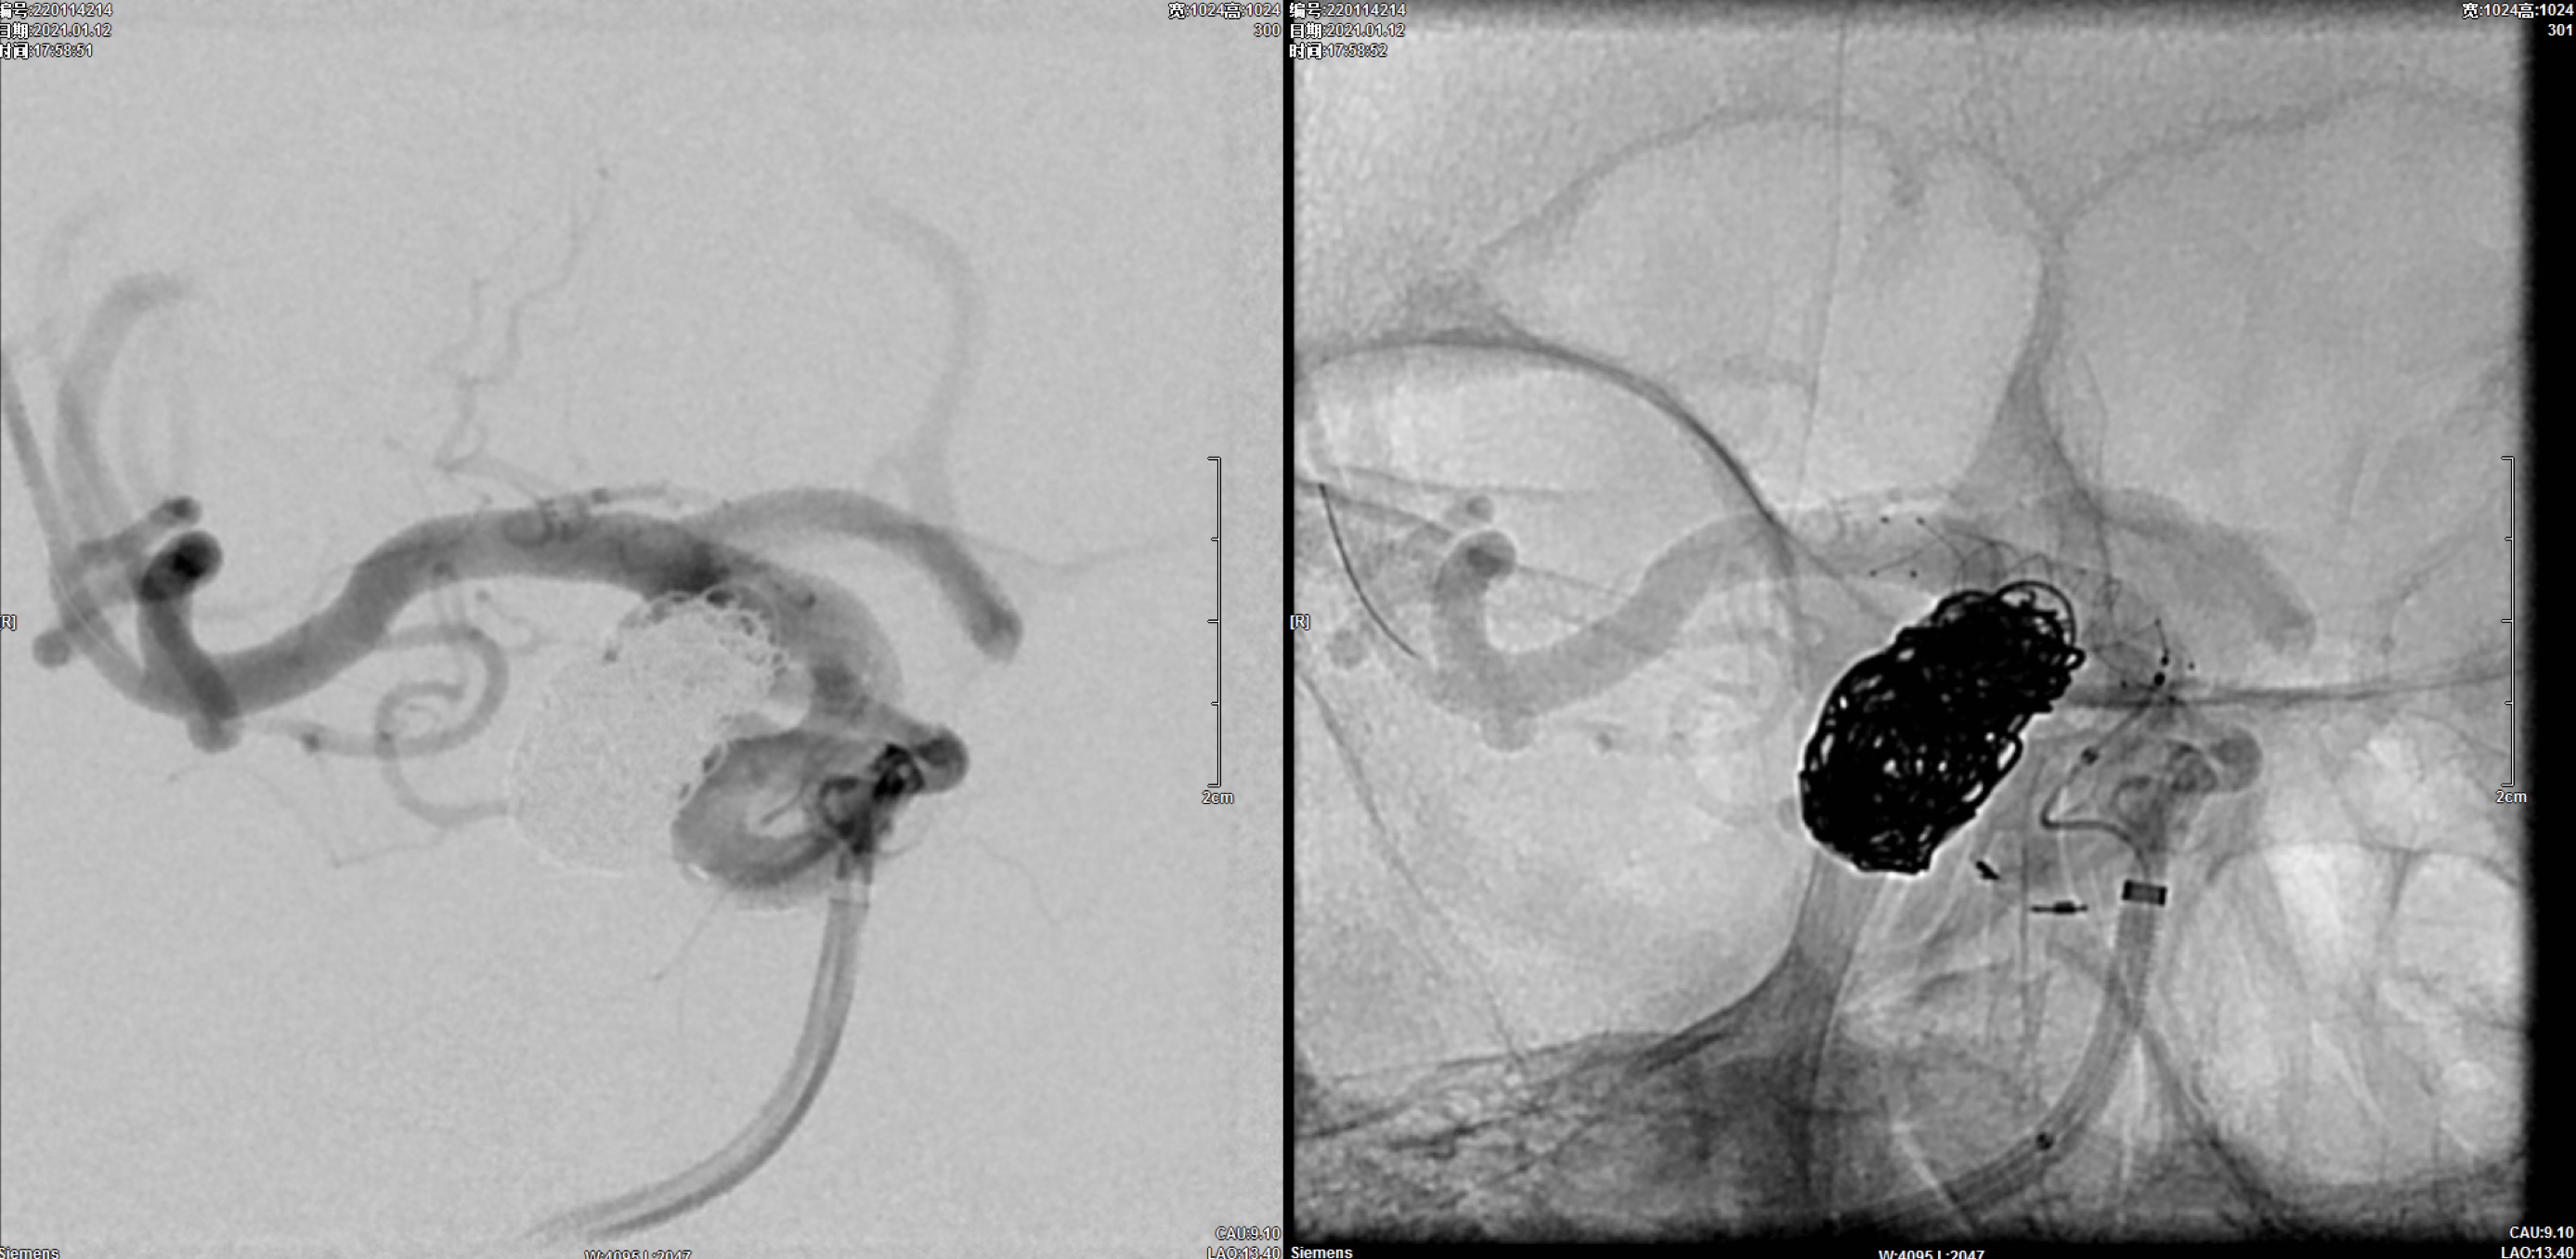

选择Lvis3.5mm*20mm支架半释放保护下经瘤腔深部栓塞微导管送入第一枚16mm*52cm弹簧圈后,经另一根栓塞微导管交替分区填塞动脉瘤瘤体!

完全释放支架后,处理瘤颈部!共送入9枚栓塞弹簧圈!

术后即刻正位造影:动脉瘤栓塞满意!

术后即刻侧位造影:动脉瘤栓塞满意!